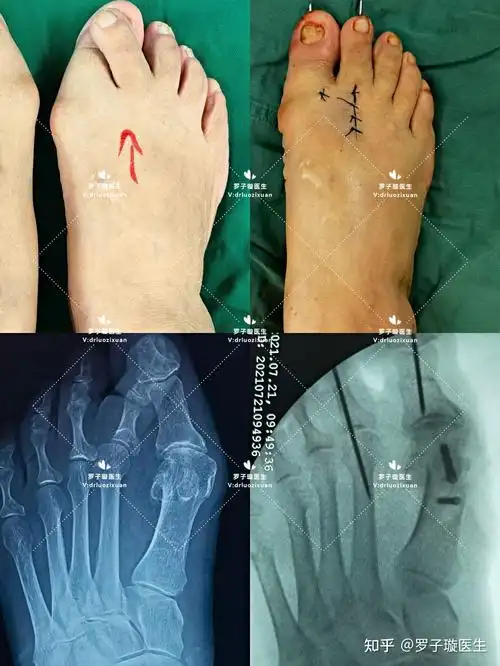

拇外翻合并严重叠趾畸形